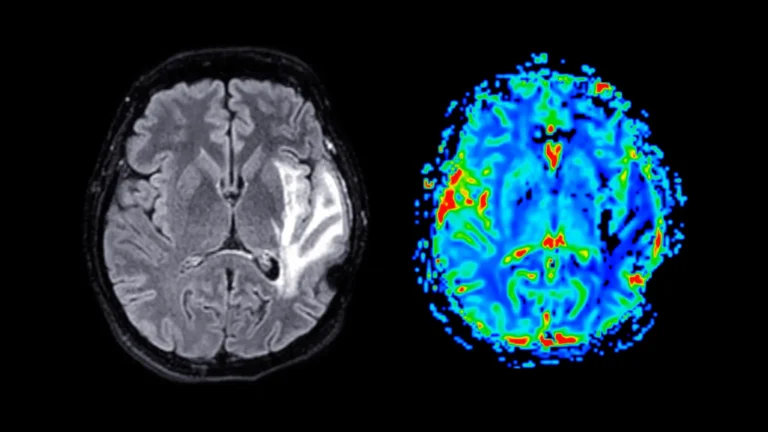

Recent scientific investigations have illuminated a potential mechanism underlying the pervasive memory deficits characteristic of Alzheimer’s disease,...

The relentless pursuit of effective strategies to combat Alzheimer’s disease (AD), a neurodegenerative condition characterized by progressive...